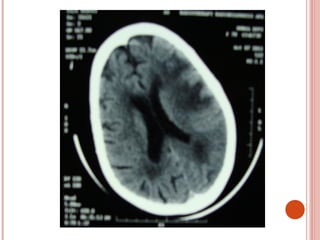

   CT Brain- Infarct involving left frontal, parietal and occipital

areas with foci of hemorrhage within infarct